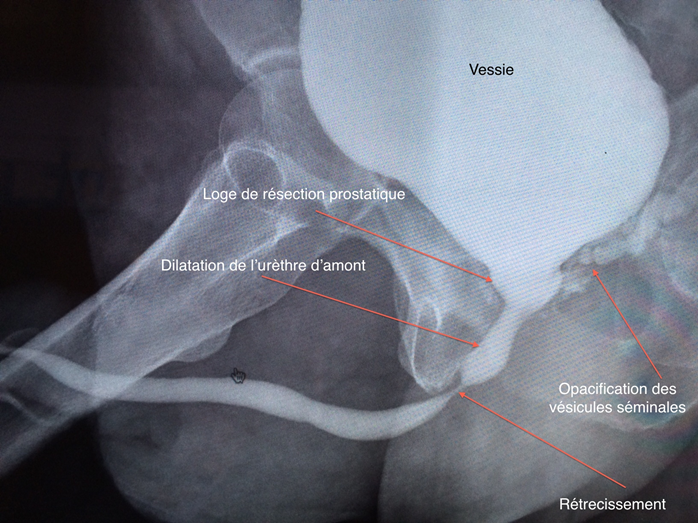

2. l’uréthro cystographie rétrograde et mictionelle

C’est un examen d’imagerie qui permet d’étudier le bas appareil urinaire et notamment la filière cervico urétrale. Il est particulièrement utile quand on suspecte un rétrécissement de l’urètre associé ou en cas de repousse ou de reliquat adénomateux dans la loge prostatique après échec d’un traitement chirurgical.

Au temps mictionnel de l’uréthro cystographie, on visualise le rétrécissement très postérieur de l’urètre bul-baire, complication d’une résection trans urétrale de la prostate.